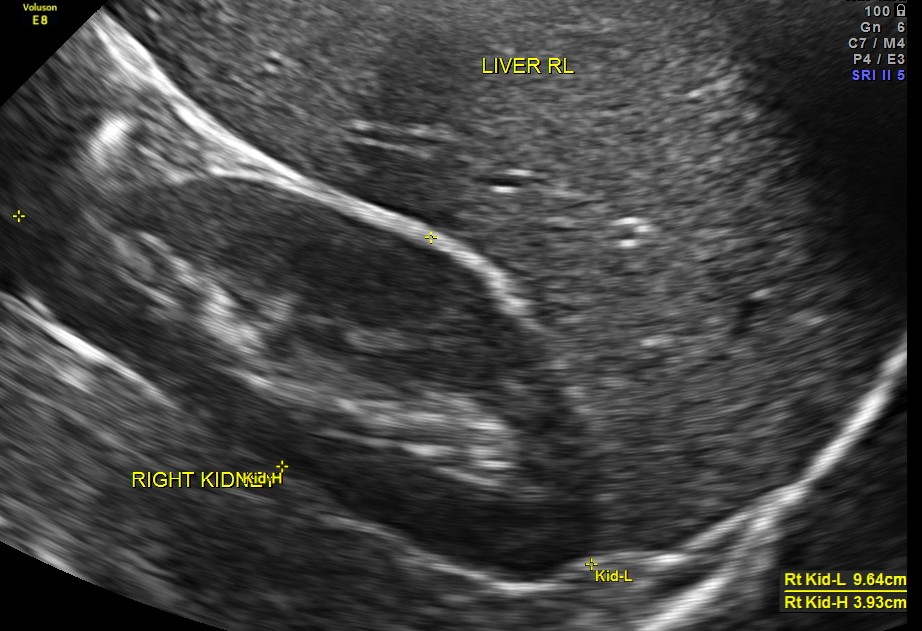

An ultrasound abdomen was done as part of evaluation of anemia.

Now for the unexpected findings . To finish off the scan , I was sweeping the aorta, IVC and the pre and post aortic regions.

This mass visualised there . This was antero-lateral to the aorta and showed mixed echotexture , with some vascularity.

This was not mobile and all i could offer was a description of what was seen with the impression of a mass of unknown origin – ?? enlarged node and advised further work up.